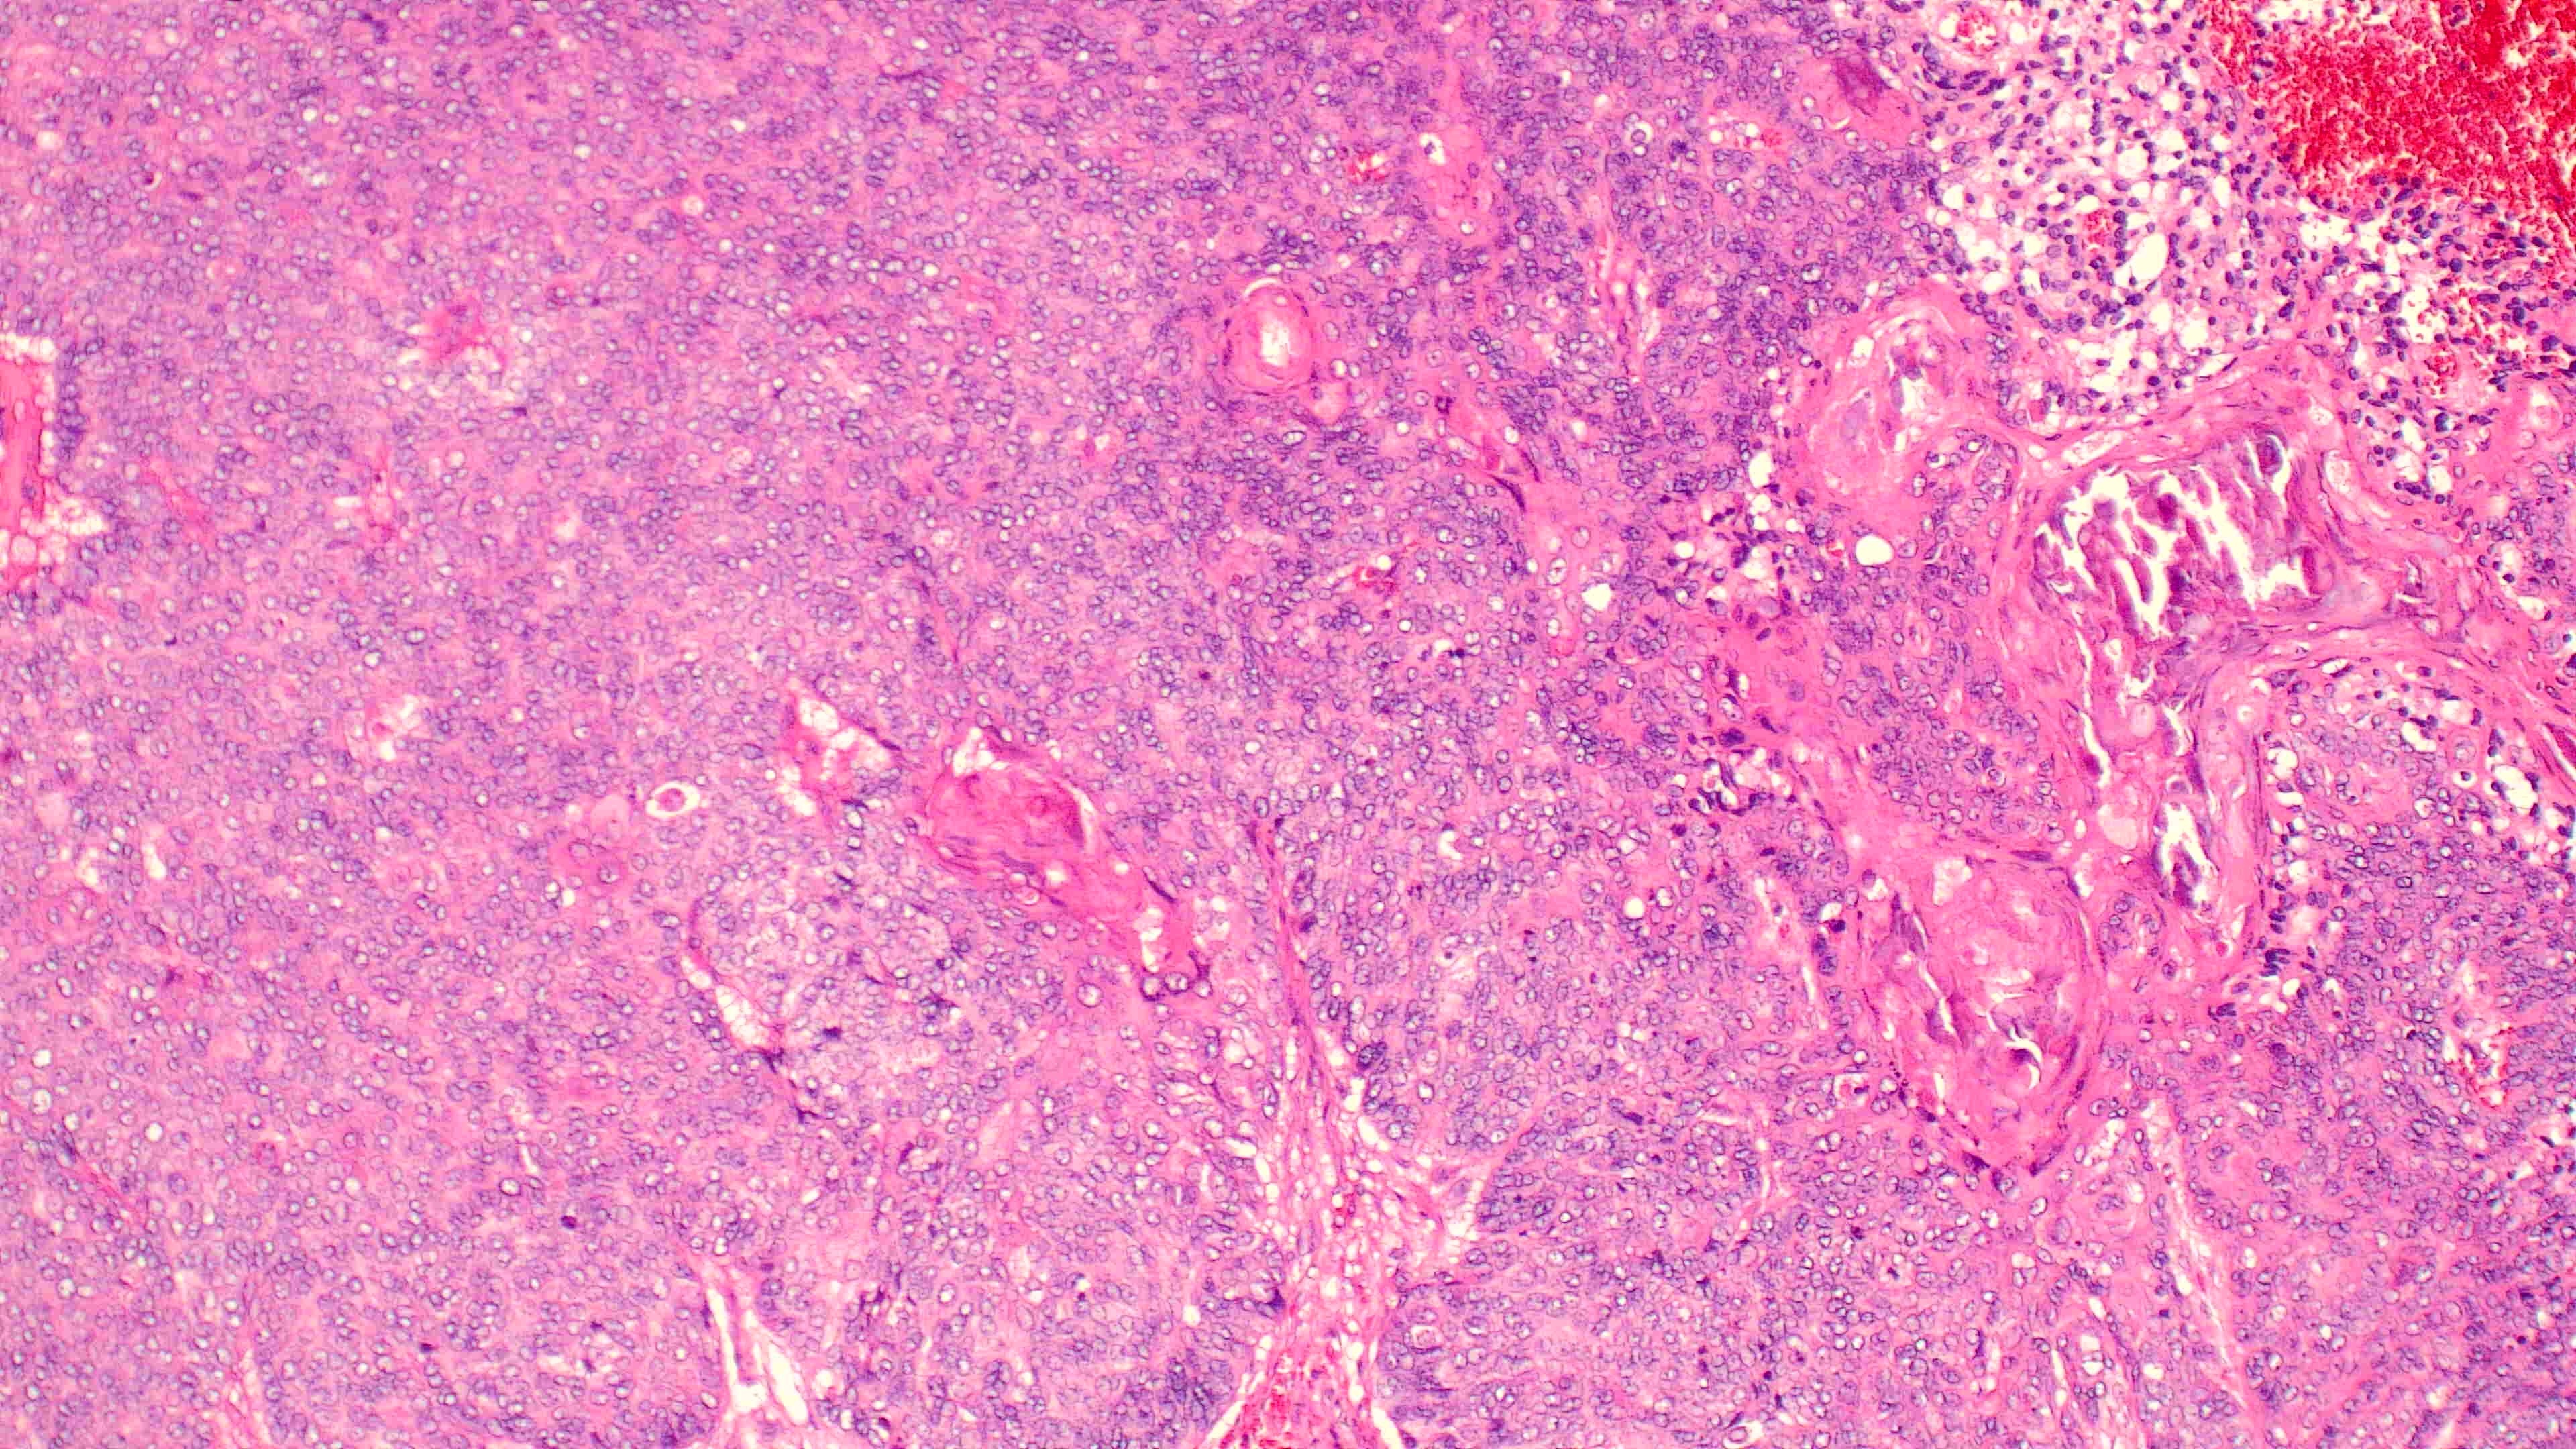

下巴肿物

性别

男

年龄

70岁

临床诊断

一般病史

0

标本名称

大体所见

带皮不规则组织3*3*2cm,切面灰白灰褐实性质软

1.考虑:来自汗腺;2.恶性?

会诊结果:小汗腺汗孔癌